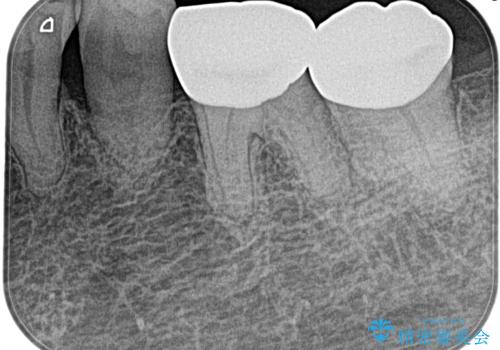

奥歯がズキズキ痛い 根管治療

- 冷たいもので強い痛みがあり、1週間前ぐらいからズキズキ痛いことを主訴に来院されました。

患歯に冷温刺激に対し20秒の持続痛と打診を認めたため、不可逆性歯髄炎の診断とし治療を行なっております。

- 精密根管治療(イニシャルケース,大臼歯):122,000円、ファイバーコア:22,000円費用は治療当時の料金となります

不可逆性歯髄炎と診断される場合は、経過観察を行なっても正常歯髄に戻る可能性は極めて低いため今回の処置のように抜髄の適応となります。